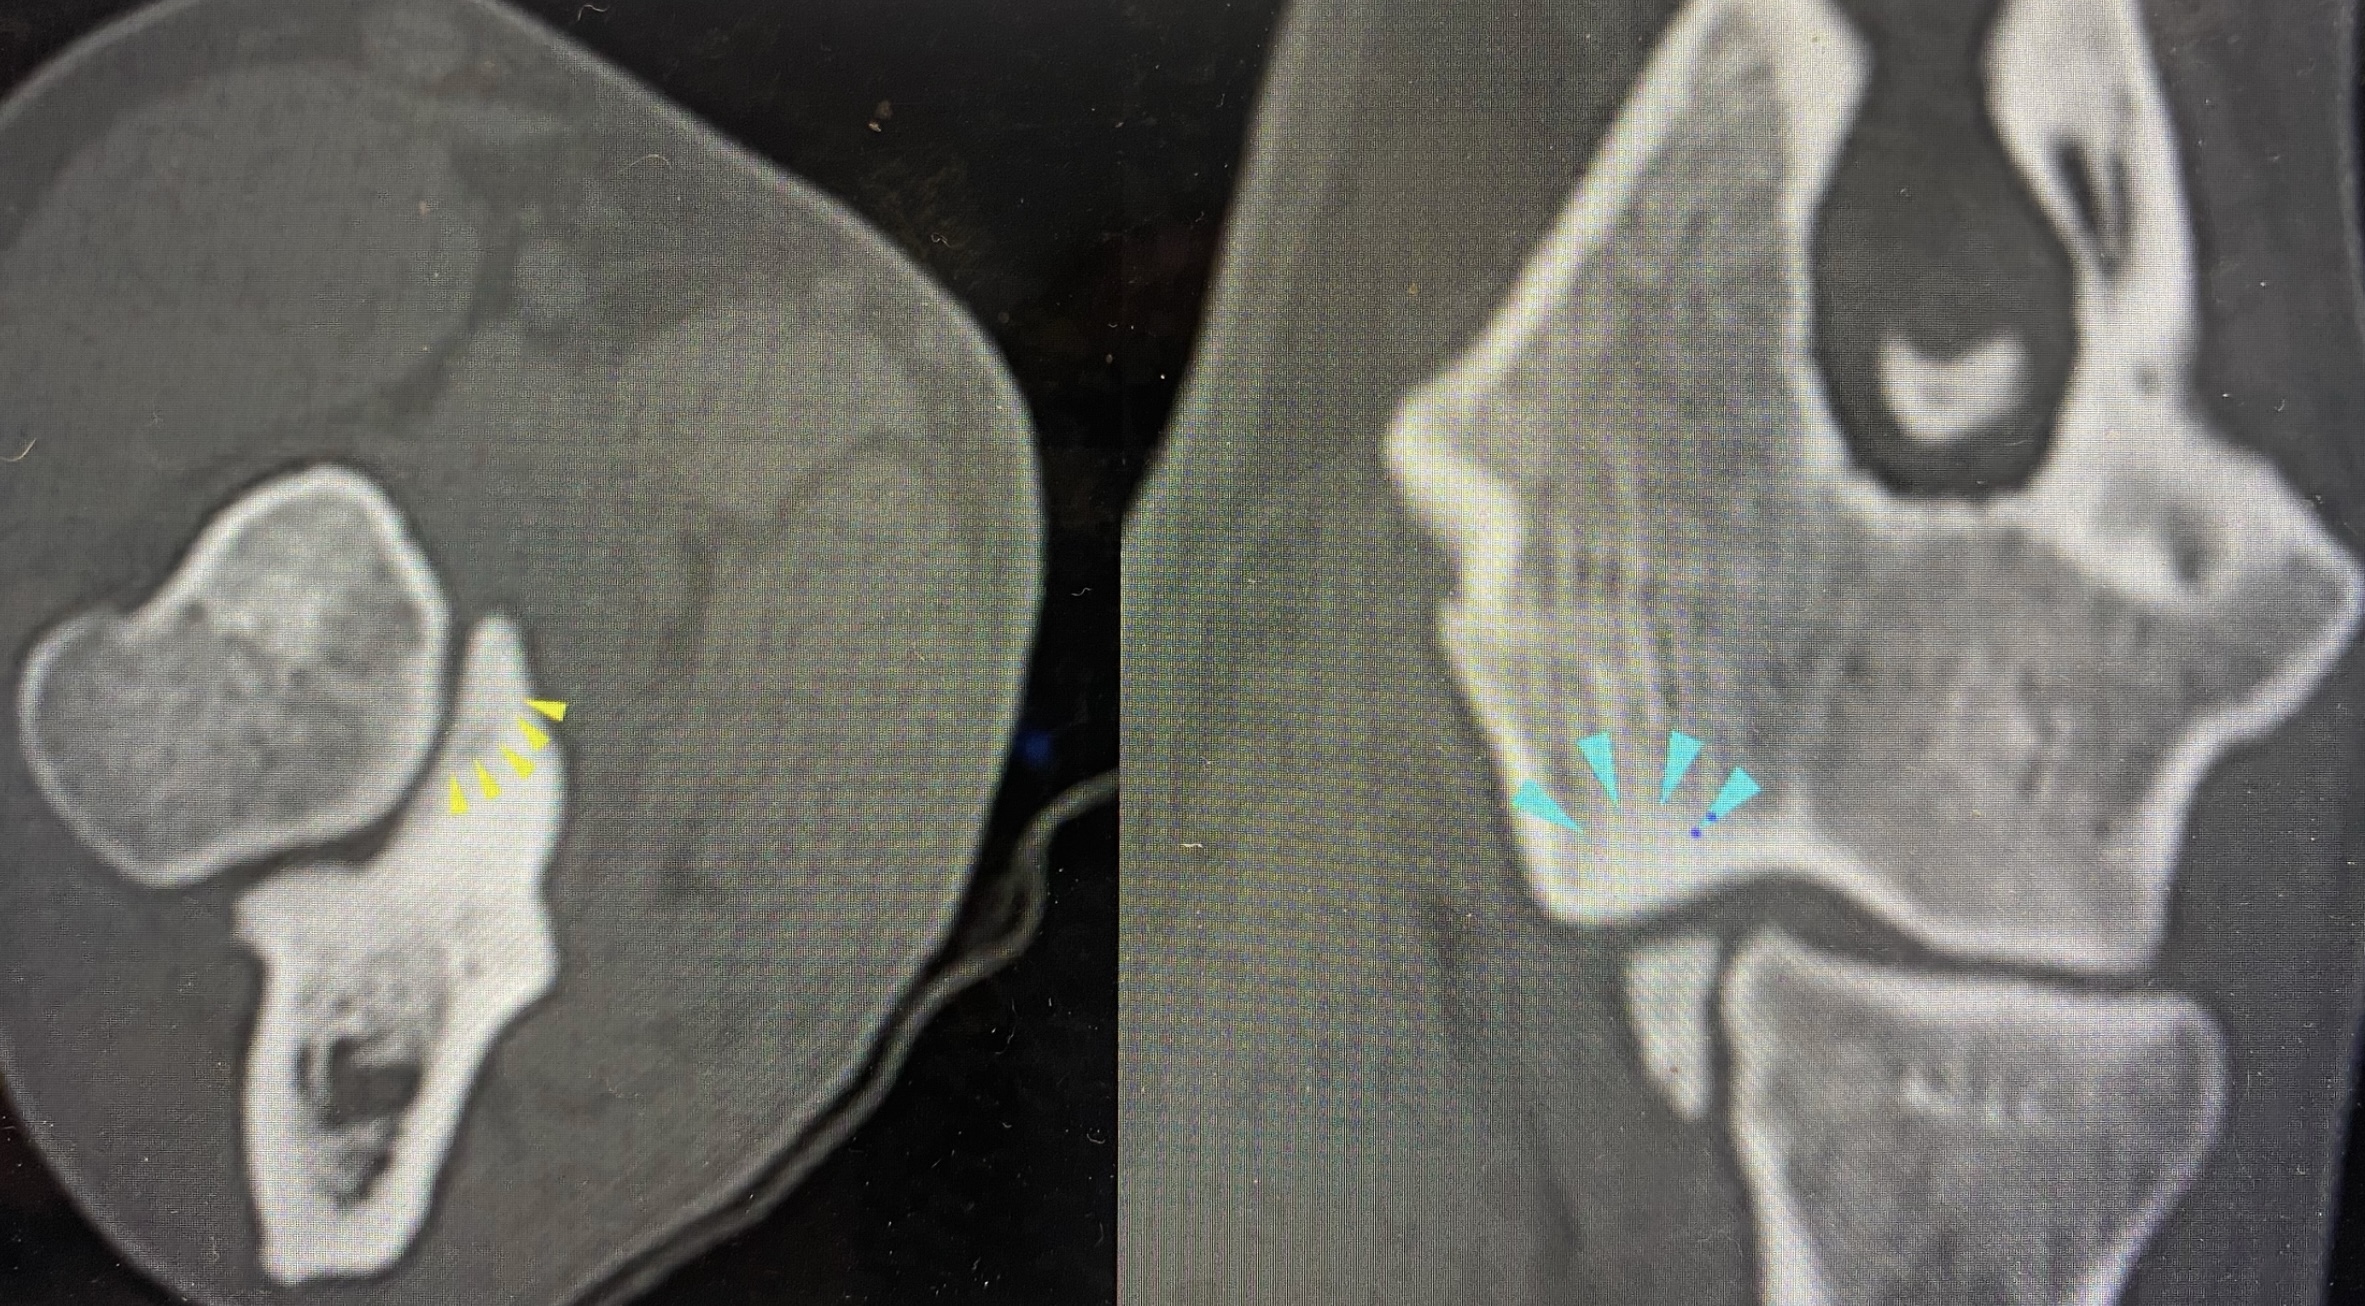

Computed Tomography (CT)

If you have a patient who you feel could benefit from a CT scan, don’t hesitate to get in touch and we can help recommend a facility in your area. If indicated, follow-up surgery can be performed back at your own clinic or if preferred, on the same day as CT examination, if the host practice allows.

We also offer a specialist CT reporting service, offering your team and clients an overview of pathology AND advice on treatment options. Please enquire to info@provetsurg.co.uk for more information including prices.